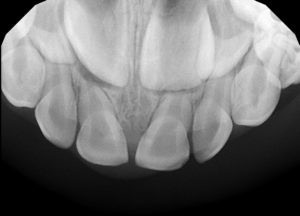

2. How old is the patient with the following X ray?